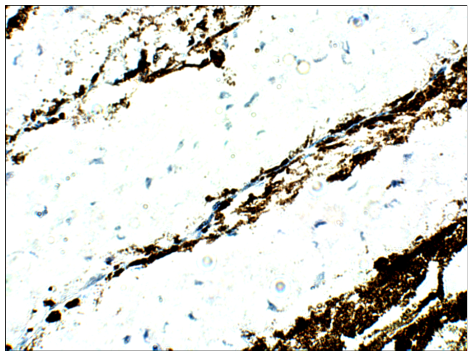

大鼠視網(wǎng)膜-PDE6β

原發(fā)抗體:PD6-201AP;在IHC阻斷緩沖液中以1:50稀釋。DAB(棕色)染色和蘇木精QS(藍(lán)色)復(fù)染。放大40倍。FFPE部分。